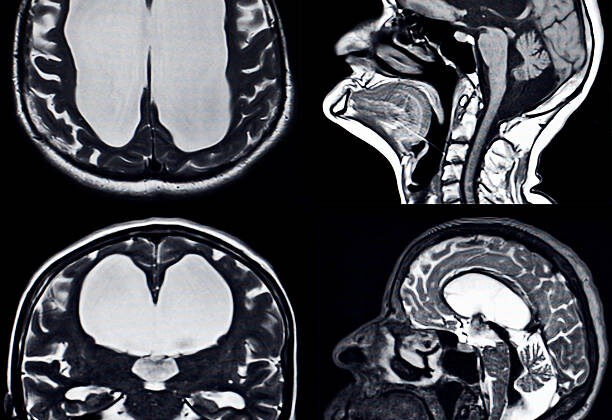

Hidrosefali Tedavisinde Şant Cerrahisi: Uzmanlar Hayati Bilgileri Paylaştı Beyinde su birikmesi olarak bilinen hidrosefali, beyin omurilik sıvısının (BOS) normal akışının bozulmasıyla ortaya çıkan ciddi bir sağlık sorunudur. Uzmanlar, bu durumun tedavisinde en yaygın ve etkili yöntemin şant cerrahisi olduğunu belirtiyor. Üsküdar Üniversitesi NPİSTANBUL Hastanesi’nden Beyin, Sinir ve Omurilik Cerrahisi Uzmanı Prof. Dr. Onur Yaman, hidrosefali tedavisindeki bu cerrahi yöntemin detaylarını anlattı.

Prof. Dr. Yaman, şantın beyin içindeki fazla sıvıyı vücudun başka bir bölgesine, genellikle karın boşluğuna, aktaran kapalı bir plastik sistem olduğunu açıkladı. “Ameliyat genel anestezi altında ortalama 45 dakika sürer. Şantın bir ucu beyin içindeki boşluğa (ventrikül), diğer ucu ise karın boşluğuna yerleştirilir. İki uç, cilt altından geçirilen bir tünelle birleştirilir ve aradaki valf sistemi sıvı akışını kontrol eder,” dedi.

Şant cerrahisi, çocukluk ve erişkinlik döneminde travma, beyin kanaması veya tümör gibi nedenlerle hidrosefali gelişen hastalara uygulanabildiği gibi, doğuştan hidrosefali vakalarında da tercih edilen bir yöntemdir. Ancak Yaman, öncelikle hidrosefaliye yol açan asıl nedenin ortadan kaldırılmaya çalışıldığını, daha sonra şant ameliyatının planlandığını vurguladı.